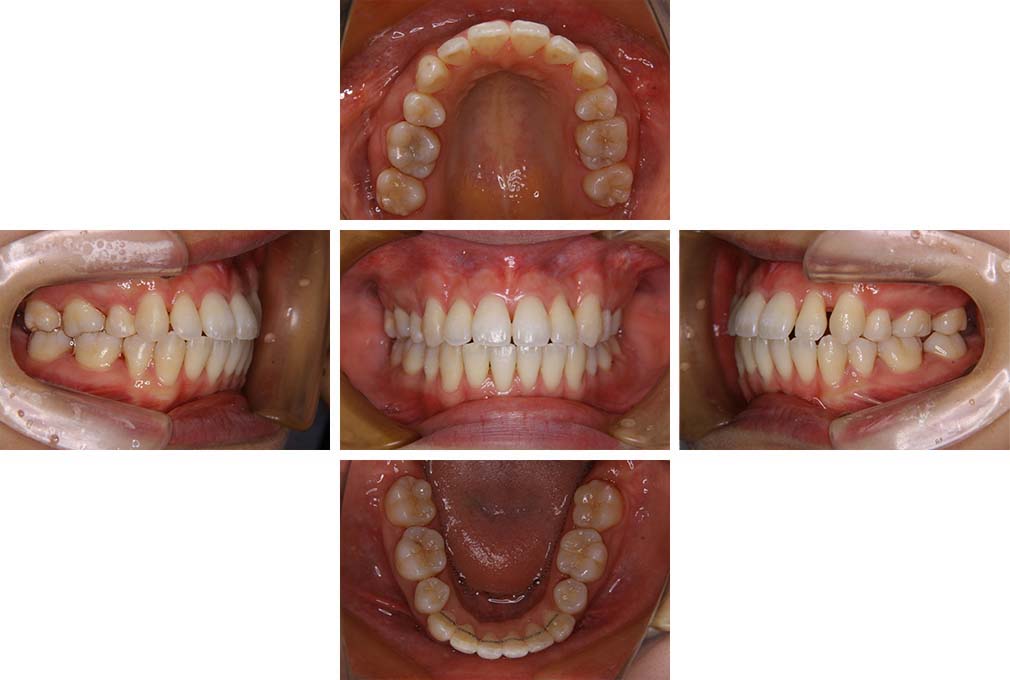

CASE:01

叢生を伴う骨格性上顎前突

初診時年齢 15歳10カ月

性別 男性

治療費の目安 約75万円程度(治療開始時)

上顎前歯の前突と叢生を主訴として来院された。大臼歯関係は左右側ともにⅡ級で上顎の方が前方に位置していた。叢生を伴う骨格性上顎前突と診断し、上下顎小臼歯抜歯を行っていただきマルチブラケット装置に顎外固定装置を併用して動的治療を行った。顎外固定装置や矯正用ゴムの使用など協力状態も良好で、動的治療期間2年0カ月、調整来院20回でマルチブラケット装置を撤去し保定へ移行した。動的治療終了後10年0カ月を経過したが保定移行時とほぼ同様の咬合状態で良好な状態を保っていた。

治療前

15歳10か月

治療後

動的治療期間2年0カ月

18歳5か月

10年経過

動的治療終了後10年0カ月

28歳5か月